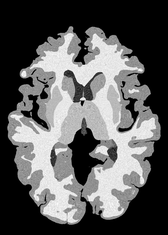

4.2 Registration to a 100 micron ex-vivo brain MRI volume

To showcase the efficacy of our method on real large scale images, we register a 250 in-vivo MRI image (Lüsebrink et al., 2017) to a 100 ex-vivo FLASH human brain volume (Edlow et al., 2019). This represents an inverse problem with more than 11.2B optimizable parameters (compared to 20M for clinical datasets), or 44.8GB of GPU memory. The entire problem does not fit on most GPUs, necessitating distributed multimodal registration. We optimize a composite transform - affine followed by a diffeomorphic mapping; details can be found in Section E.1. Multimodal deformable registration took 58 seconds on 8 NVIDIA A6000 GPUs, which is unprecedented at this resolution. Fig. 6 shows qualitative results, highlighting the ability to register highly detailed structures such as cerebellar white matter; these structures are not visible at macroscopic scales. The resultant advantages of performing registration at this scale can allow researchers to characterize the neuroanatomy at microscopic resolutions and allow morphometric analysis of cortical layers and subcortical nuclei among other structures.